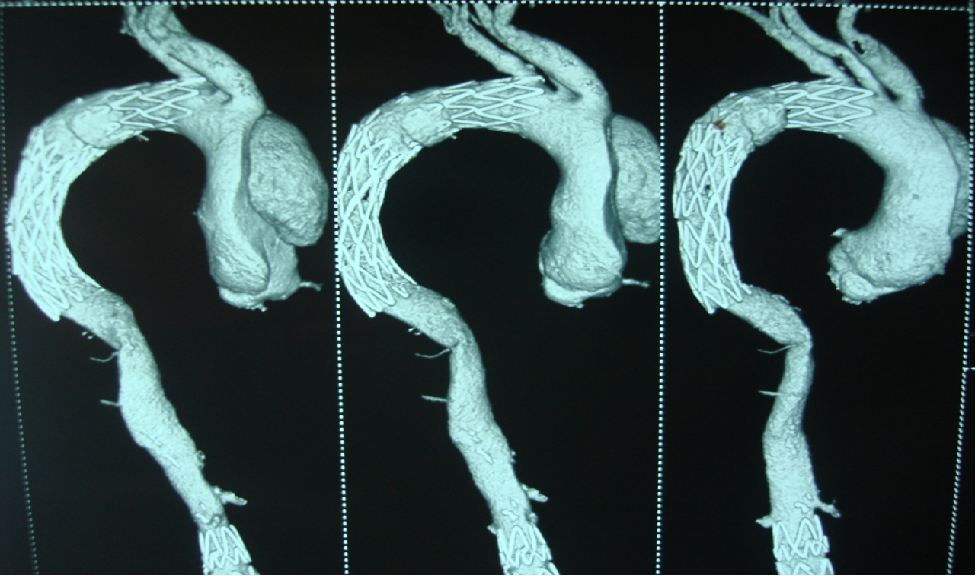

男,49岁,急性AD。2019年1月TEVAR,3月RTAD,行全弓置换+支架象鼻。2022 年1月25日术后复查,结果良好。